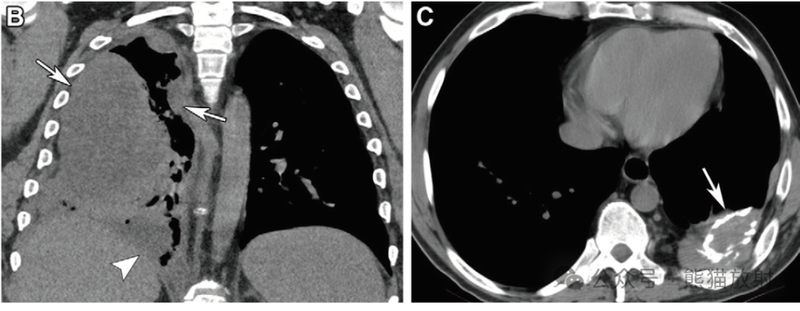

61岁男性,多房性腹膜包涵囊肿。冠状位增强CT(A) 和冠状T2WI(B)显示右下腹多房囊性肿块(箭),内可见多发轻度强化的纤细分隔。